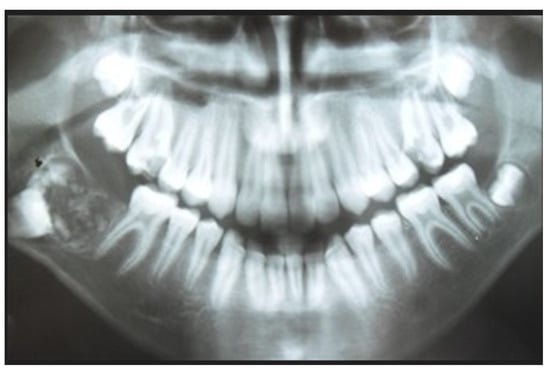

Treatment Possibilities in Mandibular Defect Reconstruction Based on Ameloblastic Fibro-Odontoma Treatment—Does Small Bone Defects Heal without Bone Grafting?

2. Case Report Presentation